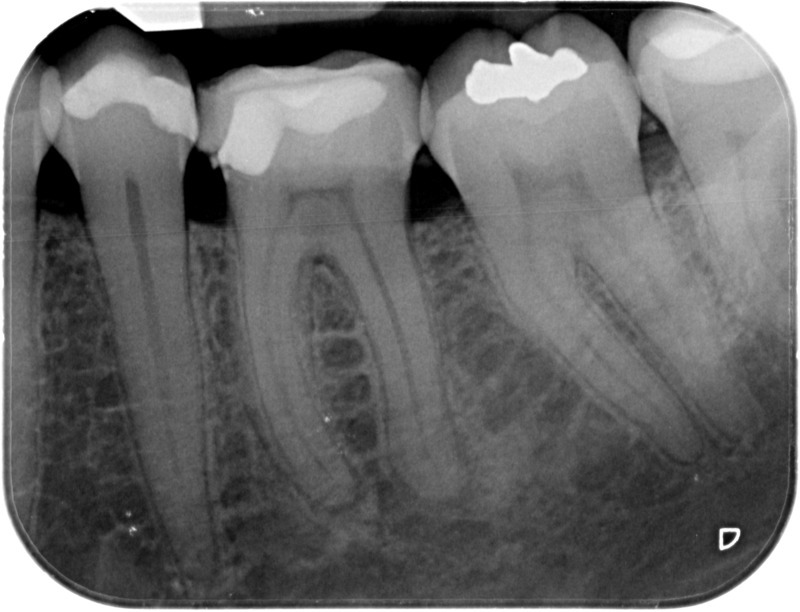

• Traitement endodontique : Sous anesthésie locale et à travers la protection d’un champ opératoire nous accédons à la pulpe de la dent à soigner, puis aux canaux de ses racines que nous devons désinfecter. Ce soin nécessite l’élimination complète de la source de contamination (souvent la carie) parfois sous une ancienne reconstitution ou une couronne qu’il faut alors retirer. Une fois le nettoyage et la mise en forme des canaux réalisés, nous les obturons de façon hermétique avec un ciment et un matériau thermoplastique appelé Gutta Percha. Ceci afin d’empêcher une nouvelle prolifération bactérienne et d’assurer le maintien de la dent dans ses structures de soutien (ligament parodontal et os alvéolaire). L’ouverture effectuée au centre de la dent sera d’abord refermée avec un pansement provisoire avant d’envisager ensemble la reconstitution d’usage : un composite, un inlay-onlay ou une couronne.

Après